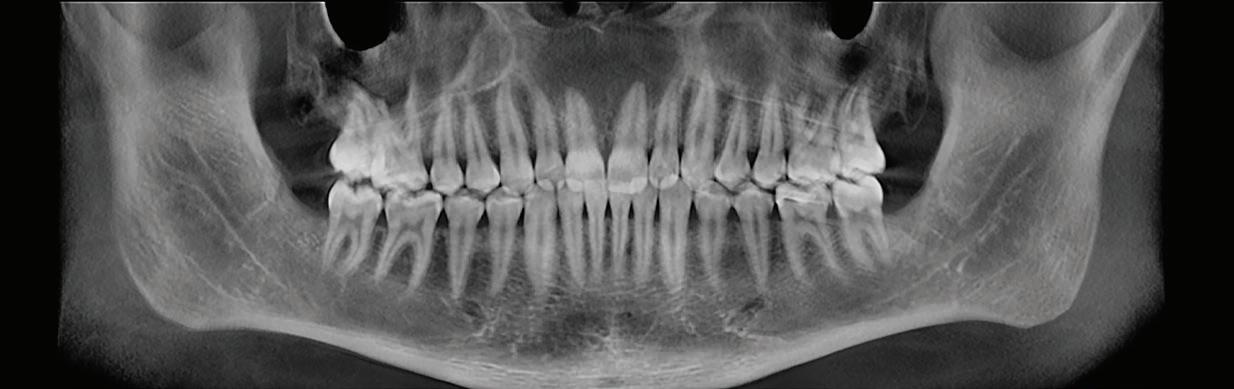

Multidisciplinary approach to diagnosis and management of lymphadenopathy in a patient with mucous membrane pemphigoid: a case report

Heba Turkstani

Eric T. Stoopler

Temitope T. Omolehinwa

Eman Alamodi

Mel Mupparapu